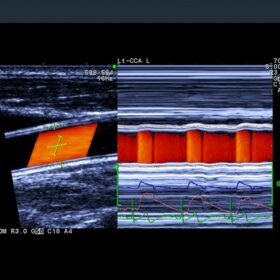

- eTRACKING (Echo Tracking)

- Arterial Stiffness

- Flow Mediated Dilatation (FMD)

- Wave Intensity (WI)

- Automated Intima-media Thickness (IMT) Measurement

- Transit Time of Vessel Flow (TVF)